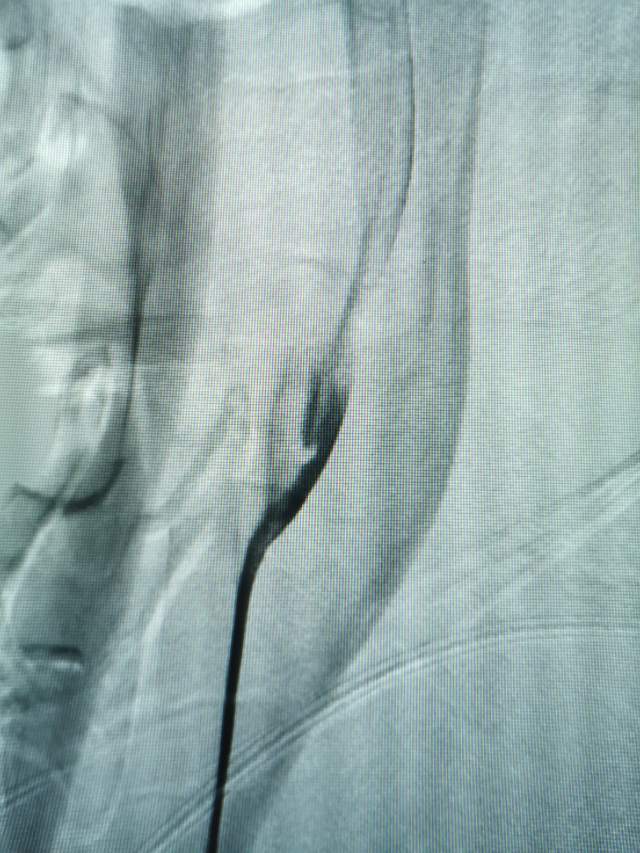

因此,这个左侧脑梗塞与左侧颈动脉蹼(左侧颈内动脉的起始部感觉被人砍了一刀)相关,属于症状性蹼,长期口服抗血小板药物无效,进行外科干预是审慎的和妥当的。